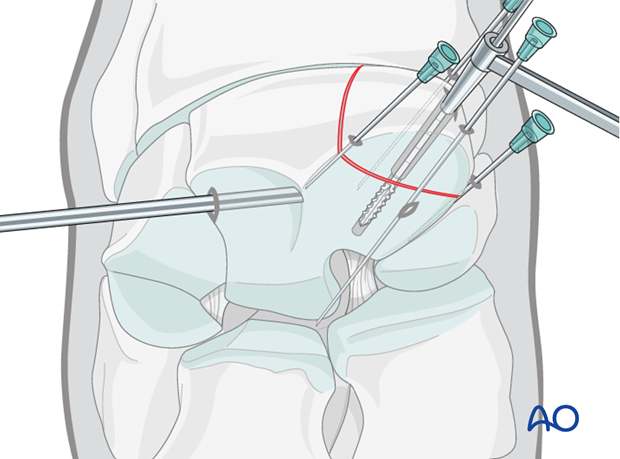

The 4.5 mm screw of appropriate length is inserted. The screw is tightened under arthroscopic visualization. After the screw is tightened any debris or elevated cartilage is removed from the fracture line.

Intraoperative radiographs are take to confirm screw length and correct positioning.

Use two fingers and thumb when doing final tightening, thereby avoiding excessive torque and potential breaking of screw head, especially if 3.5 mm implants are used.

Intraoperative radiographs are taken to confirm screw length and correct positioning.